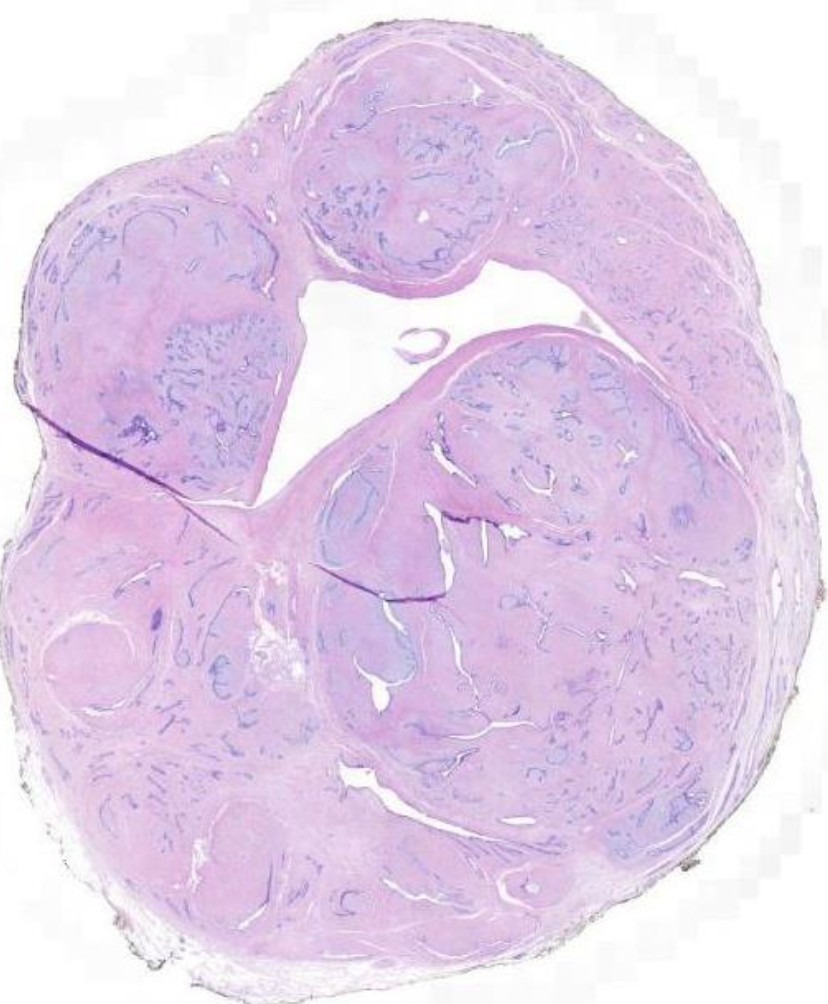

Diagnose?

Duktales Carcinoma in situ